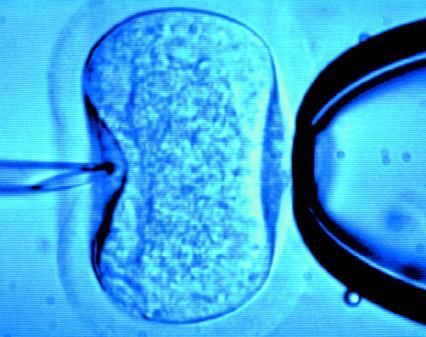

《Lacent》杂志于2012年1月12日在线发表了一项最新研究。该研究指出在不考虑年龄的情况下,在体外受精(IVF)过程中双胚胎移植可比单胚胎移植获得更高的活胎出生率。

本研究对超过100,000名进入IVF周期的女性进行了检测,结果显示相比40岁以下的女性,年龄大于40岁的女性在接受双胚胎移植时围产期并发症风险较低。然而在上述2个年龄组的女性中,三胚胎或多胚胎移植均会增加并发症的风险,且未提高活胎出生率。

先前的随机对照研究主要聚焦于年龄小于40岁的女性,而本研究具有前瞻性,并评估了活胎出生率或围产期不良结果与胚胎移植数目之间的相关性是否受孕妇年龄的影响。

研究者对2003年1月至2007年12月之间参加随机对照试验的个体数据进行了分析,所有资料取自英国人工受精与胚胎管理局。该数据库包含124,148名进入IVF周期的女性,活胎分娩为33,514例。研究者在年龄为40岁及其上下的女性中分别比较了活胎出生率、多胎生育率、低出生体重率(< 2.5 kg)、早产率(< 37周妊娠)和严重早产率(< 33周妊娠)。

在双胚胎移植的体外受精(IVF)过程中,与年龄小于40岁女性相比,年龄大于或等于40岁的活胎生产比值比较高(前者为2.33 [95% CI,2.20-2.46],交互作用P值为0.0006,后者为3.12 [95% 可信区间(CI),2.56-3.77])。

在双胚胎移植(ET)过程中,与低龄女性相比,高龄者的活胎生产绝对风险差值较小(40岁以上者为0.090,95% CI,0.080-0.099;40岁以下者为0.156,95% CI,0.148-0.163,P < 0.0001);且高龄女性中多胎分娩、低出生体重和早产等围产期并发症的绝对风险和比值较低。

三胚胎移植时,低龄女性组活胎出生率降低(三胚胎与单胚胎移植比值为0.120,95% CI,0.100-0.140);高龄女性组活胎出生率也并未增加。同时,低年龄组和高年龄组的围产期并发症发生风险均升高。

本文作者为来自英国布里斯托大学的Debbie Lawlor博士和来自英国格拉斯哥大学医院部的Scott Nelson博士。作者表示:“根据某些机构的推荐意见,胚胎移植数目应当受到限制。但在美国和欧洲分别有40%和21% IVF女性接受了至少三个胚胎移植。在IVF治疗过程中,20%-30%女性为双胎或多胎妊娠。”作者调整了母亲年龄、不孕时间、产科或不孕治疗史、不孕原因、激素刺激、治疗周期数目、以及是否应用胞浆内精子注射等因素后进行了多变量分析。

作者在文中写到:“我们的研究结果在一定程度上支持对40岁以上女性进行双胚胎转移方案,因为与低龄女性相比,高龄女性的胎儿早产或低体重的风险较低,且双胚胎移植与活胎出生率最优相关。”考虑到三胚胎转移可增加围产期并发症的风险,作者补充到:“我们的研究清楚地表明,不应对任何年龄的女性进行三胚胎移植。”

Background Elective single-embryo transfer has been proposed as a strategy to reduce the risk of multiple birth and adverse pregnancy outcomes after in-vitro fertilisation (IVF). Whether this approach should be restricted to young women is unclear.

Methods In a prospective study of UK Human Fertilisation and Embryology Authority data, we investigated whether perinatal livebirth outcomes varied by the number of embryos transferred in relation to maternal age. We compared rates of livebirth, multiple births, low birthweight (<2·5 kg), preterm birth (<37 weeks), and severe preterm birth (<33 weeks) in women younger than 40 years and those aged 40 years or older. We used logistic and binomial regression methods to assess, respectively, relative risk and absolute differences in risk.

Findings We assessed 124 148 IVF cycles overall, which yielded 33 514 livebirths. The odds ratios of livebirth were higher in women aged 40 years or older than in those younger than 40 years when two embryos were transferred compared with one embryo (3·12, 95% CI 2·56—3·77 vs 2·33, 2·20—2·46; p=0·0006 for interaction), but the absolute difference in risk of livebirth was smaller (0·090, 0·080—0·099 for women ≥40 years vs 0·156, 0·148—0·163 for those <40 years; p<0·0001). The odds ratios and absolute risk differences for multiple birth, preterm birth, and low birthweight were all smaller in older than in younger women (analyses were done in 32 732 cycles in which a livebirth had resulted and data on gestational age and birthweight were complete). Livebirth rates did not increase with transfer of three embryos, but the risk of adverse perinatal outcomes did increase.

Interpretation Transfer of three or more embryos at any age should be avoided. The decision to transfer one or two embryos should be based on prognostic indicators, such as age.